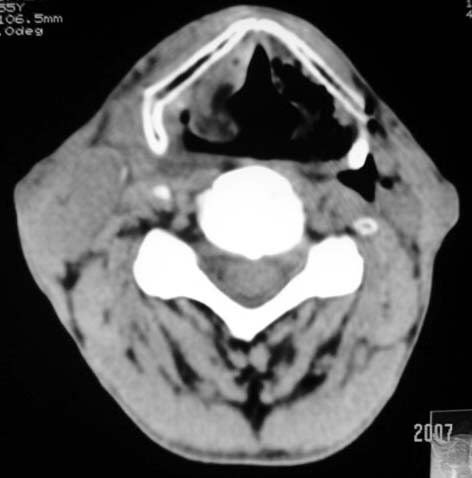

以下是引用dyqct在2007-4-20 16:19:00的发言:[br]考虑:1、左侧梨状窝区破裂伴左颈深、浅部气肿。[br] 2、右侧甲状腺区血肿(请追问病史是否伤及右颈部)。[br] 3、建议病情稳定后增强扫描除外右侧甲状腺腺瘤。